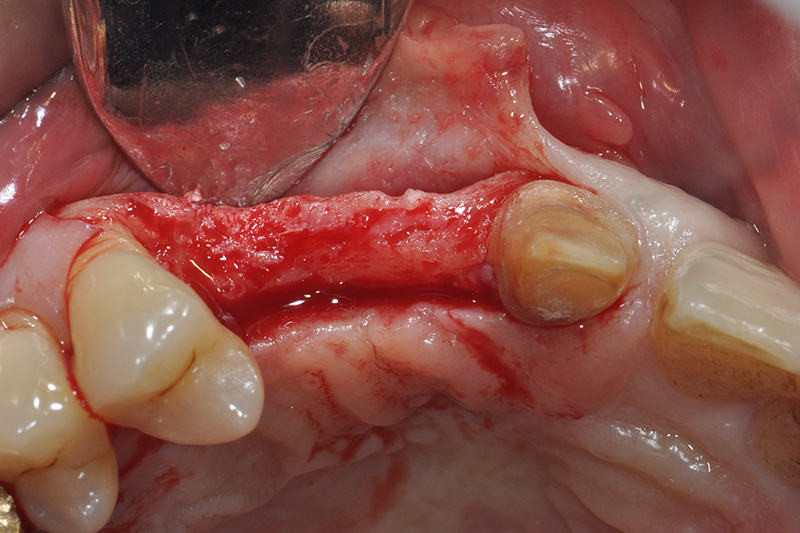

缺牙多顆

案例一

術中